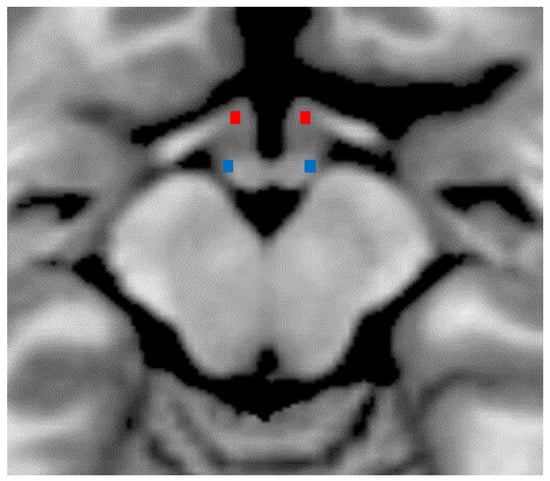

Descriptive and inferential data on DTI metrics for hypothalamic ROI are summarized in Table 2. Bilateral hypothalamic regions of interest are shown in Figure 1. The factor “group” was significant for whole hypothalamus ROI and for the posterior left and right hypothalamus ROIs. Compared to HC, patients with MI showed significantly higher MD (p < 0.001, Cohen’s d = 5.58), AD (p < 0.001, Cohen’s d = 6.01), and RD (p < 0.001, Cohen’s d = 5.24), with lower FA (p = 0.001, Cohen’s d = −2.34). In the exploratory analysis, MD (left: p < 0.001, Cohen’s d = 2.78; right: p < 0.001, Cohen’s d = 2.14), AD (left: p < 0.001, Cohen’s d = 2.66; right: p < 0.001, Cohen’s d = 2.03), and RD (left: p < 0.001; Cohen’s d = 2.85; right: p < 0.001, Cohen’s d = 2.40) were significantly higher, and the FA was lower (left: p = 0.01; Cohen’s d = −1.30; right: p = 0.001, Cohen’s d = −1.90) in the posterior hypothalamic region bilaterally. We did not detect between groups differences in the anterior hypothalamic region (Table 3).

Figure 1.

Bilateral anterior (in red) and posterior (in blue) hypothalamic regions of interest are shown on axial slice of an MRI template (T1-weighted MNI 2 mm).

The data analysis method is detailed elsewhere [18]. Images were pre-processed using the FSL toolbox DTIFIT based on a diffusion tensor model to yield FA (fractional anisotropy), MD (mean diffusivity), RD (radial diffusivity), and AD (axial diffusivity). The initial region of interest (ROI) covered the whole of the hypothalamus [30]. Thereafter, according to the coordinates provided by Boes et al. [31], for each subject, we defined 4 further ROIs covering the bilateral anterior hypothalamus—mostly with neuroendocrine function—and the bilateral posterior hypothalamus, including the wake-promoting nuclei (see Figure 1 and the resulting masks in.nii files format are available for public download at the following link: osf.io/37kxr, accessed on 26 October 2022).

Based on Baroncini et al. [30] and Boes et al. [31] methods, all ROIs were drawn using a T1-weighted template (MNI152 2 mm voxel in FSL software) by two expert neuroradiologist (E.T. & F.C). The center of gravity coordinates in MNI space for the anterior hypothalamic region are x = ±4.4; y = 1.33; z = −14.67, the posterior hypothalamic ROI coordinates are x = ±6.6; y = −7.33; z = −12.67, and those of the whole hypothalamic ROI are x = 0.136; y = 4.68; z = −11.9. The size of the hypothalamic ROIs in the 2 mm space was 6 voxels (48 mm3), 3 per hemisphere, equally for the anterior and posterior ROIs (Figure 1). For each participant and every hypothalamic ROI, we calculated mean FA, MD, RD, and AD values in the hypothalamus by averaging those voxels in the ROI.